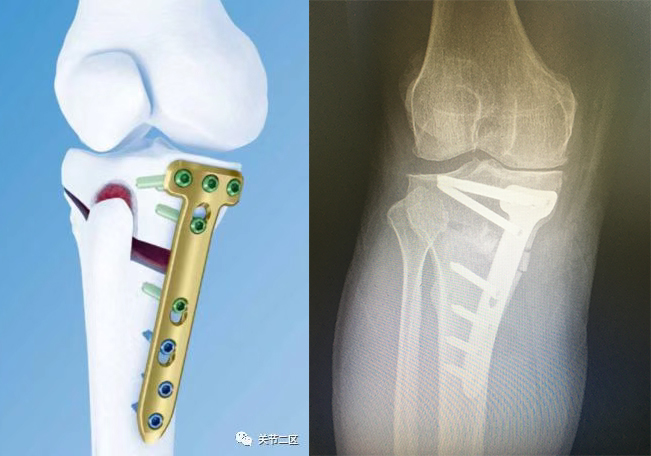

崔先生因右膝关节疼痛1年,加重2月来院就诊,查体及辅助检查诊断为“右膝骨性关节炎”。崔先生想要保留自身膝关节,骨科一病区医生团队讨论后,决定由徐伟敏主任医师和孙波副主任医师为患者实施右胫骨高位开放截骨+自体髂骨植骨术治疗。术后第二天在患肢支具的保护下即可负重下地行走,膝关节疼痛明显缓解,患者对治疗效果非常满意。

膝关节痛目前已经成为困扰中老年人日常生活最主要的因素之一,很多中老年人膝关节内侧疼痛,活动受限,同时伴有“O”形腿,需要借助手杖或助行器行走,严重影响生活质量。 “大夫,我的腿疼该怎么治” “是不是需要关节置换手术” “哪种保膝治疗适合我” 给大家介绍一种无痛、创伤小、康复快的“保膝”新疗法! 胫骨高位开放楔形截骨术 相对于膝关节置换来说,保膝治疗能够更多地保留人体膝关节自身的本体感觉。 保膝:胫骨高位截骨 换膝:单髁、全膝关节置换 · 优势 · 1.术后疼痛少; 2.创伤小,第二天膝关节即可恢复功能; 3.可保留自身膝关节; 4.关节活动度更好。 · 适用人群 · 1.关节外畸形的患者; 2.前内侧膝关节骨关节炎的患者; 3.胫骨近端内翻角小于85°的患者; 4.小于65岁的患者; 5.活动量大、希望保留更多膝关节自身功能的患者。